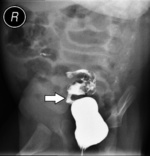

– Poddaliśmy dziecko znieczuleniu ogólnemu, by wykonać bardzo szczegółowe badanie radiologiczne. Musieliśmy ustalić na sto procent, jak wygląda to domniemane zwężenie. Przygotowałem wcześniej odpowiednie narzędzia, to znaczy odpowiednich rozmiarów cewnik z balonem, którym miałem zamiar rozszerzyć zwężenie, jeśli ono tam rzeczywiście będzie. Skoro już miałem na stole operacyjnym śpiącego pacjenta, trzeba było to wykorzystać – mówi dr Bysiek i dodaje: – Rzeczywiście, badanie radiologiczne potwierdziło, że jest zwężenie. Z duszą na ramieniu – bo jelito dziecka jest bardzo delikatną strukturą – drogą przez odbyt, pod kontrolą radiologiczną umieściłem dziecku balonik w jelicie.

Zastosowano balonik w kształcie walca, jaki stosuje się w operacjach na drogach żółciowych. Delikatnie nadmuchano, aż do rozwarcia zwężenia. Po wyjęciu z jelita cewnika wraz z balonem przeprowadzono badanie kontrastowe i okazało się, że jelito trzyma ten poszerzony rozmiar. Jelito jest rozciągliwe i podatne, jednorazowe rozszerzenie wystarczyło, by przywrócić drożność.

– Oczywiście będziemy chłopca kontrolować, bo nie wiadomo, czy ten zabieg wystarczy na całe życie – mówi dr Bysiek. – Cieszę się, że pomogliśmy dziecku, choć to nie było nic nadzwyczajnego, żadne odkrycie. Po prostu spróbowałem zastosować znaną metodę, używaną najczęściej przez kardiologów inwazyjnych przy udrażnianiu naczyń wieńcowych, ale niestosowaną nigdy dotąd do udrażniania jelita. Udało się (ryc. 1-2).